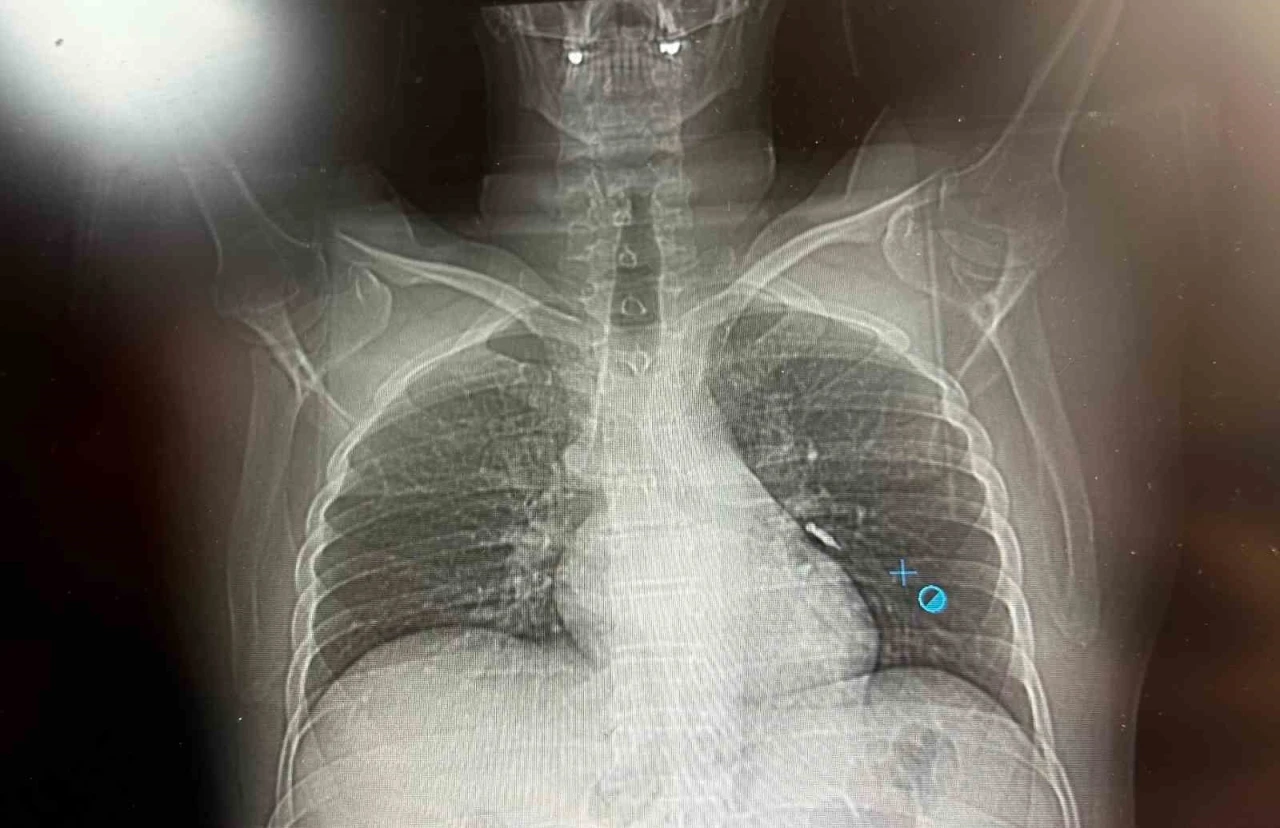

Göğüs Cerrahisi uzmanları Dr. Sadullah Aksoy ve Dr. Beniz İrem Ersoy Şığva tarafından hastaya bronkoskopi işlemi uygulandı. Sol akciğerin üst lobunda saplanmış şekilde tespit edilen vida, vidalı yapısı ve bulunduğu konum nedeniyle güçlükle yerinden oynatılabildi. Yapılan uzun ve titiz müdahale sonrası vida yerinden çıkarılamasa da hasta bir süre sonra geçirdiği öksürükle birlikte implant vidasını midesine gönderdi. Vida, daha sonra doğal yollarla vücuttan atıldı. "İmplant tamamen çıkarılamadı ancak yerinden oynatılabildi"

Konuya ilişkin konuşan Göğüs Cerrahi Op. Dr. Sadullah Aksoy, bir diş merkezinde diş tedavisi sırasında hastanın çenesine yerleştirilen implantın vida kısmının işlem esnasında yanlışlıkla aspire edildiğini belirtti. İlk olarak hastanenin ek hizmet binasında çekilen tomografi sonucunda, vidanın sol akciğerin hava yollarının yaklaşık dördüncü dalına kadar ilerlediği tespit edildiğini ifade eden Op. Dr. Aksoy, "Geçtiğimiz cumartesi günü öğle saatlerinde tarafımıza ulaşıldığında, hastanın Van Eğitim ve Araştırma Hastanesi’ne yönlendirilmesini istedik. Burada acil bronkoskopi planı yapılarak hasta kabul edildi. Hasta geldiğinde genel durumu iyiydi; solunumunu tamamen engelleyen bir bronş tıkanıklığı söz konusu değildi. Aynı gün hastamızı hazırladık. Bronkoskopi sırasında, implant vidasının sol üst lobun anterior segment bronşuna saplanmış pozisyonda olduğunu gördük. Üroloji bölümünde taş çıkarma işlemlerinde kullanılan cihazla müdahale ettik. İlk denemede implant tamamen çıkarılamadı ancak yerinden oynatılabildi. Bunun üzerine bir süre bekleyip hastayı yeniden bronkoskopi için hazırlamaya başladık. İşlem yaklaşık 3,5-4 saat sürdü ve saat 18.30 civarında hasta işlemden çıkarıldı" dedi. "İmplant vidası öksürük sonrası akciğerden çıktı"

Daha sonra hasta için yeniden bronkoskopi planladıklarını ancak bu süreçte hasta şiddetli bir öksürük geçirdiğini anlatan Aksoy, "Şiddetli öksürük sonrası yapılan kontrol akciğer filminde implant vidası görünmedi. Bunun üzerine toraks ve batın BT (bilgisayarlı tomografi) görüntülemesi istedik. Sonuçlarda implantın akciğerden çıktığı ve vücutta herhangi bir yerde bulunmadığı tespit edildi" diye konuştu. "İyileşme süreci sorunsuz tamamlandı"